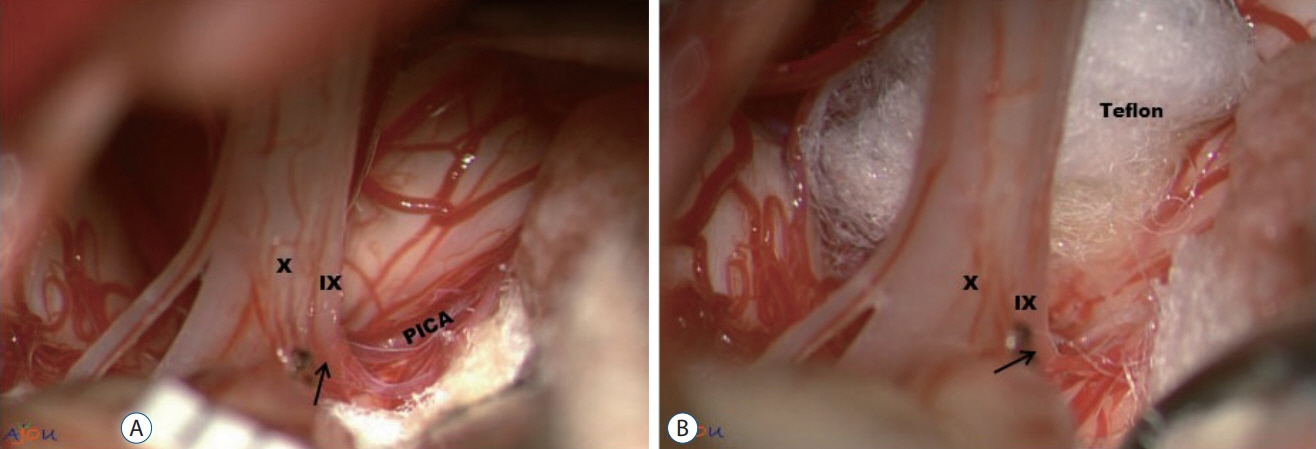

- Glossopharyngeal neuralgia (GPN) is a rare disease that must be differentiated from trigeminal neuralgia. The purpose of this article is to provide a comprehensive review of anatomy, pathophysiology, diagnostic criteria, and several options of treatment for GPN. Lessons learned through our experience of treating GPN are presented in detail, as well as cases of misdiagnosis and diagnostic pitfalls. Microvascular decompression (MVD) should be primarily considered for medically intractable GPN. Techniques employed in MVD for GPN are categorized and described. Especially, we underscore the advantages of the ‘transposition’ technique where insulating material is positioned ‘off’ the root entry zone (REZ), instead of ‘on’ it. We believe this ‘off-the-REZ’ technique can fundamentally prevent recurrence, if applicable. In addition, Gamma Knife radiosurgery can be an alternative option when a patient is ineligible for MVD, though it is categorized as a destructive procedure.